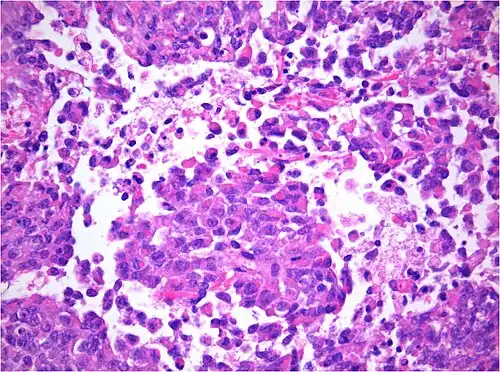

AT/RT and rhabdoid tumor share the term "rhabdoid" because under a microscope, both tumors resemble rhabdomyosarcoma.

AT/RT Histology with numerous rhabdoid tumor cells -

The tumor histopathology is jumbled small and large cells. The tissue of this tumor contains many different types of cells including the rhabdoid cells, large spindled cells, epithelial and mesenchymal cells, and areas resembling primitive neuroectodermal tumor (PNET). As much as 70% of the tumor may be made up of PNET-like cells. Ultrastructure characteristic whorls of intermediate filaments are seen in the rhabdoid tumors (as with rhabdoid tumors in any area of the body). Ho and associates found sickle-shaped embracing cells, previously unreported, in all of 11 cases of AT/RT.[24]